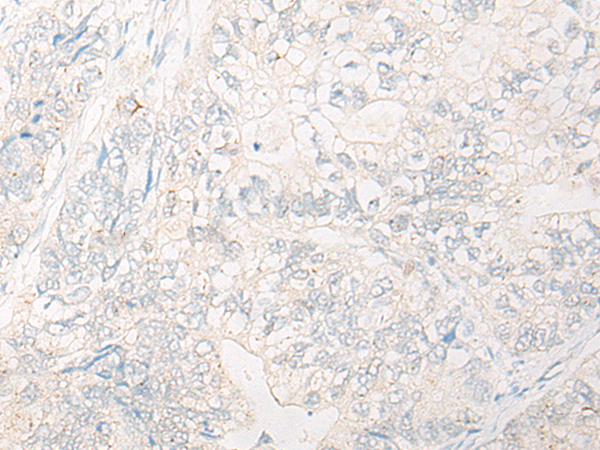

分类: 科研抗体货号: P13159别名: HNRPR; hnRNP-R应用: IHC反应种属: Human